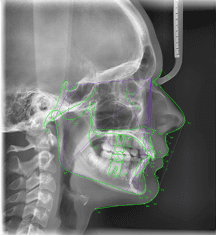

Quant aux praticiens pratiquant l’orthodontie, ils peuvent s’appuyer sur VistaSoft Trace, un module d’analyses céphalométriques rapide qui identifie automatiquement les points de référence et les silhouettes des tissus mous pour la simulation des traitements.